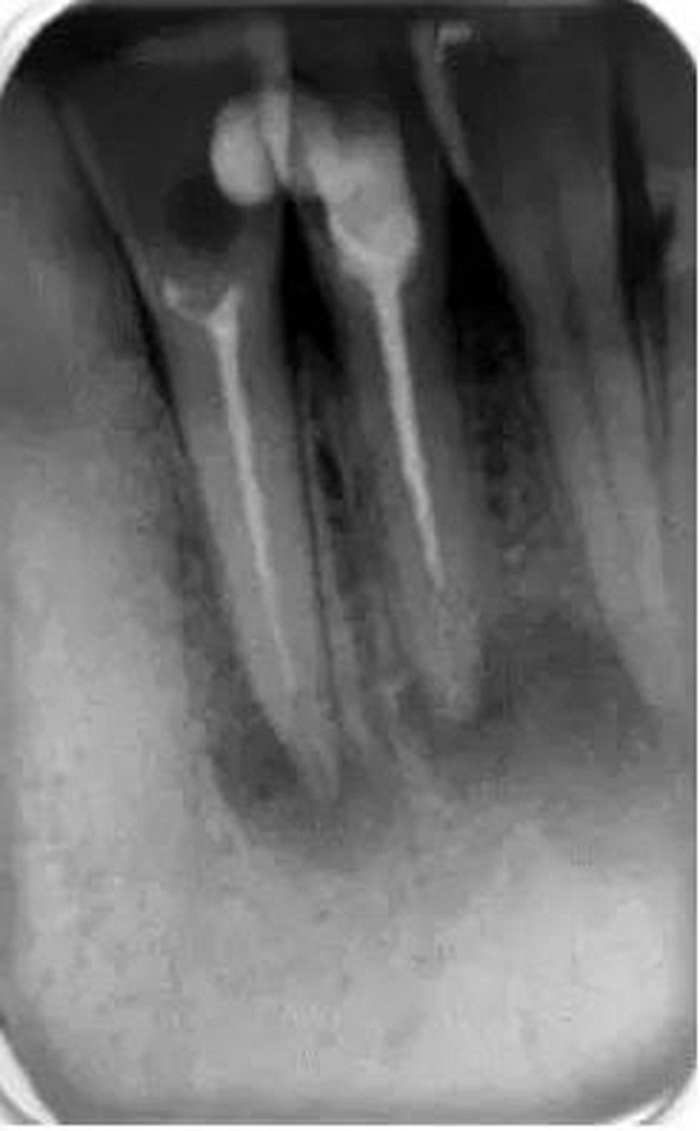

它還有助于臨床醫(yī)生決定他是否有能力進(jìn)行該病例的治療還是應(yīng)該將患者轉(zhuǎn)診到??漆t(yī)生處進(jìn)行治療。還可以在治療前明確髓腔內(nèi)是否有髓石以及牙齒或根管內(nèi)是否有其他阻塞物(如樁、釘、分離的儀器或根填充材料)(圖2)。這是很重要的,因?yàn)樗鼤?huì)給臨床醫(yī)生一些預(yù)后和治療中可能出現(xiàn)的一些問題的提示。所有這些因素必須在治療前與患者進(jìn)行溝通,以便其決定是否要繼續(xù)進(jìn)行根管治療。